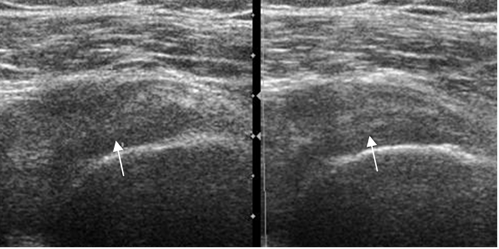

Fig 129. Tendinitis crónica del supraespinoso.

Ecografía coronal. Tendón del supraespinoso engrosado, por inflamación crónica.